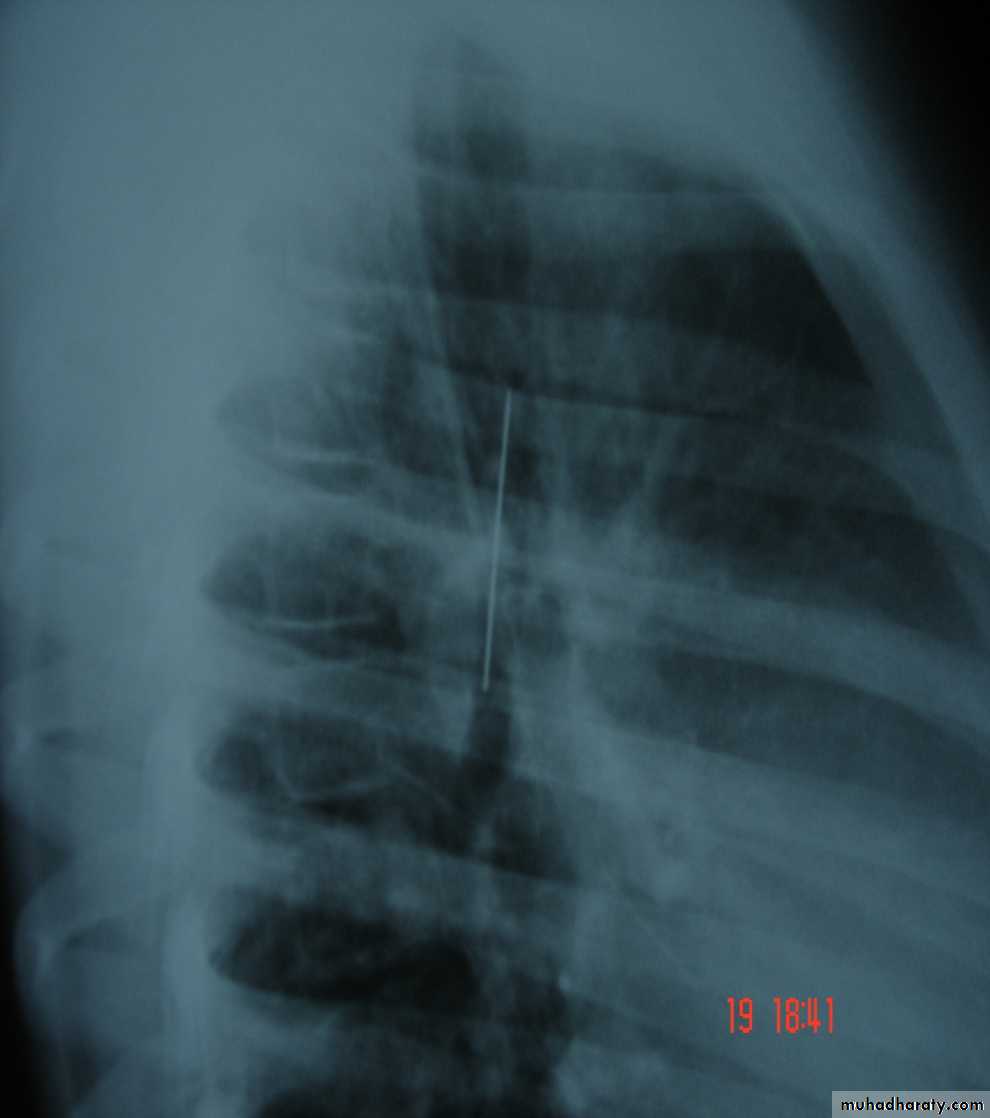

• Pulmonary Echinococcosis (Hydatid Cyst)

• Hydatid disease of the lung is caused by the small tape worm (Taenia Echinococcus ) or (Echinococcus Granulosis) .Hydatid cyst means cyst full of water .It has a life cycle between dogs & sheep .Parasites in the elementary tract of the dog shed ova that excreted in the dog faeces , contaminated the food of the sheep in which hydatid cyst will develops in the viscera . Including the lung .Infected sheep when slaughtered and its entrails are eaten by dogs , the life cycle is completed .When a human being hands or food become contaminated with canine fecal material containing ova which will be ingested .The parasitic larva burrow through the gastric mucosa and are carried to the liver in the portal venous circulation where most of them filtered out to form hydatid cyst of the liver , some escape the liver & lodge in the lung to form one or more hydatid cyst which grows slowly or rapidly over years .

• The cyst consists of a germinal layer & cyst fluid containing broad capsule & scoleses . A cellular white hyaline layers are laid down outside the cyst so that the cyst is enclosed by a laminated cyst membrane .As the cyst enlarged , it usually reaches the pleural surface . Compression of the lung tissues produces a thin fibrous layer of atelectatic lung tissue around the cyst (capsule , pericyst or adventia)

• Treatment

• Surgical• A-Inoculation means to remove it intact.

• B-Aspiration &evacuation technique

• C-Wedge resection or excision of the cyst with adjacent lung tissue.

• D-Segmentectomy ,Lobectomy or Pneumonectomy (rare ).